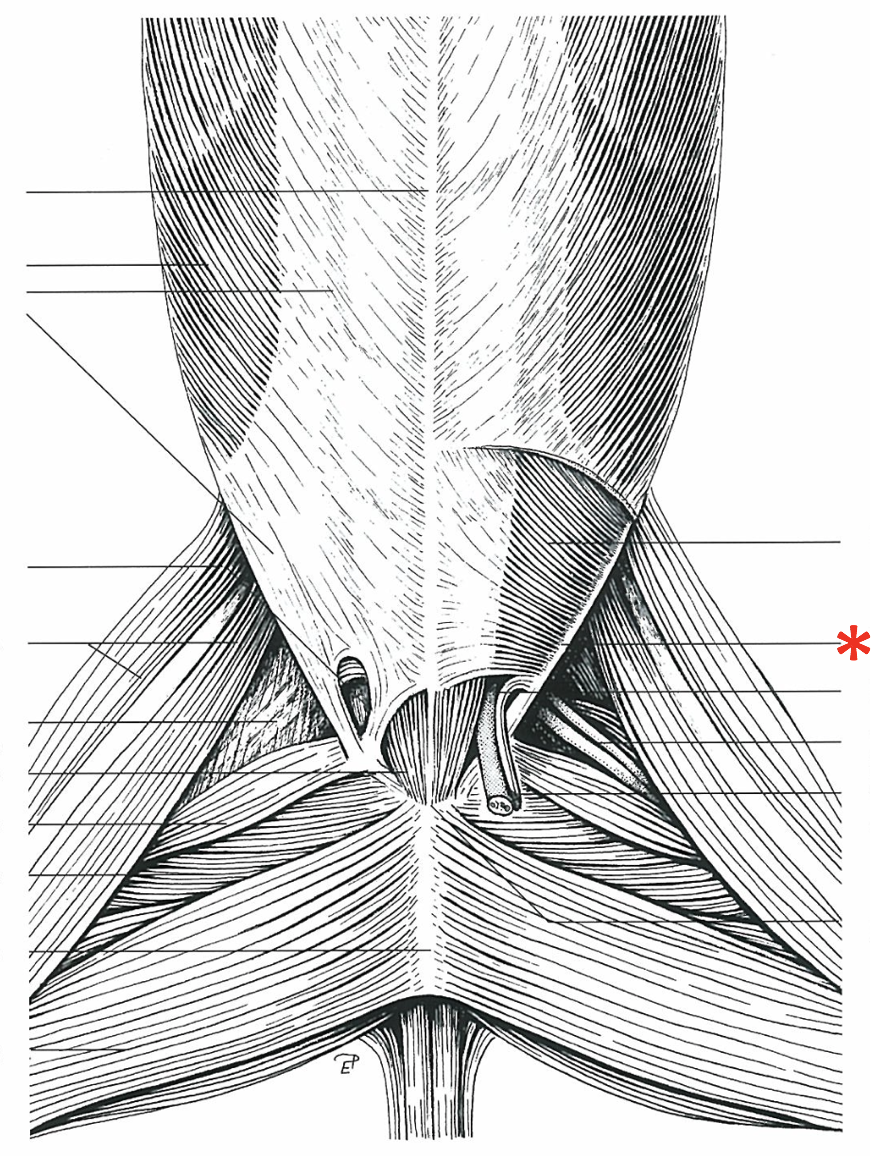

**Anulus inguinalis superficialis**

26

**M. obliquus internus abdominis**

27

**M. obliquus externus abdominis**

28

**Tunica vaginalis**

29

**Proc. vaginalis**

30

**Lig. teres uteri**